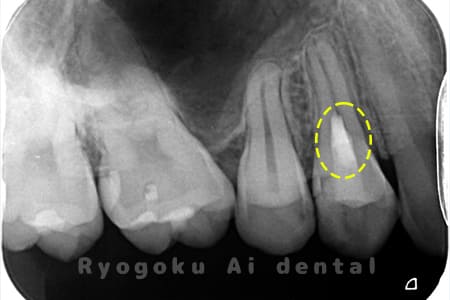

Case03

-

- 原因

- むし歯

- 治療期間

- 補綴装着期間を含めて3回

- 治療内容

- 断髄治療

- 治療費用

- 66,000円

違和感があるとのことでレントゲン撮影を行なったところ、プラスチックの被せ物の中で虫歯が広がっていると判断。レントゲンの状態からも神経にかなり近いため、患者様と相談し、断髄治療を行なったケースです。3年間のフォローアップ期間中で現在トラブルはなし。

<リスク・副作用>

術後は痛み、腫れ、痺れなどの副作用が生じる場合があります。症状が再発する可能性があります。その場合は抜髄する必要があります。